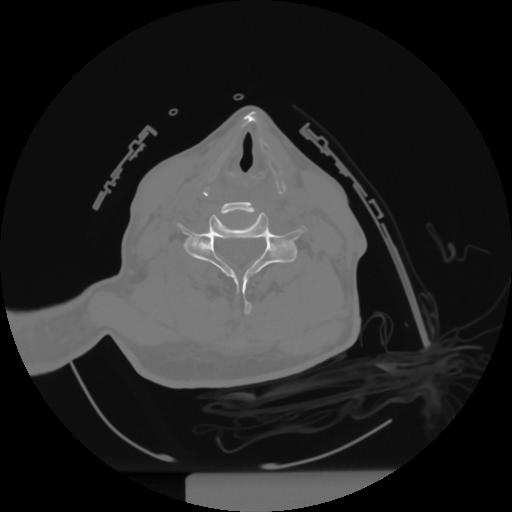

12 P.BLANDAS,,Vol,0.5,P.BLANDAS,,